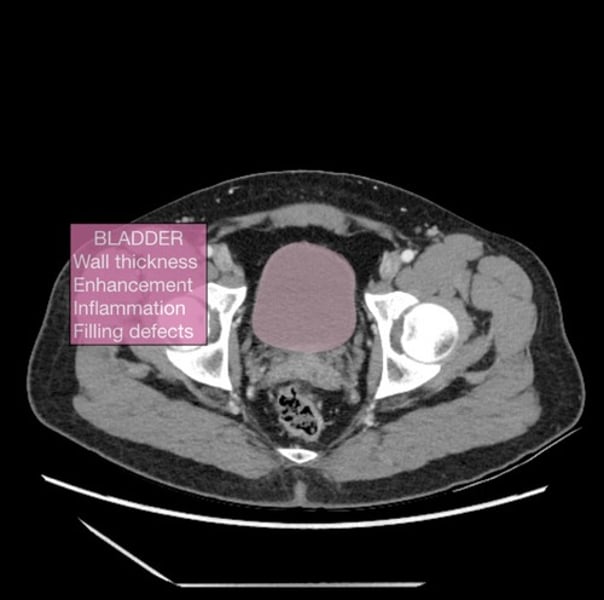

what is a cystoscopy?

visual examination of the urinary bladder using a cystoscope

what is a bladder scan?

hand-held ultrasound device, which can perform a quick, easy and non-invasive scan of the bladder

- calculates bladder volume